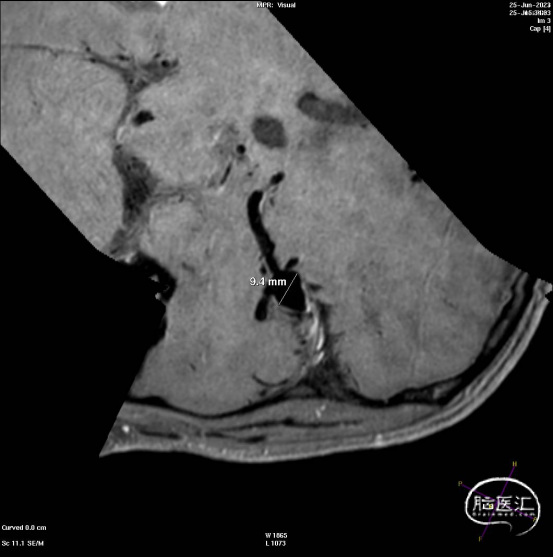

患者男性,57岁。

主诉:突发头痛14小时。

现病史:入院前14小时前,患者无明显诱因出现头痛,性质呈持性性胀痛,无晕厥,无四肢抽搐、口吐白沫、二便失禁、无双手麻木、无肢体偏瘫、言语不利,无口角歪斜等,病后就诊于当地医院,住院完善头颈部CTA提示:1.蛛网膜下腔出血;2.右大脑中动脉M1段动脉瘤。现为求进一步治疗就诊于我院,门诊以“右侧大脑中动脉M1段动脉瘤破裂伴蛛网膜下腔出血”收入我科住院治疗。

术后6个月随访造影,动脉瘤闭塞,WEB™完全栓塞。